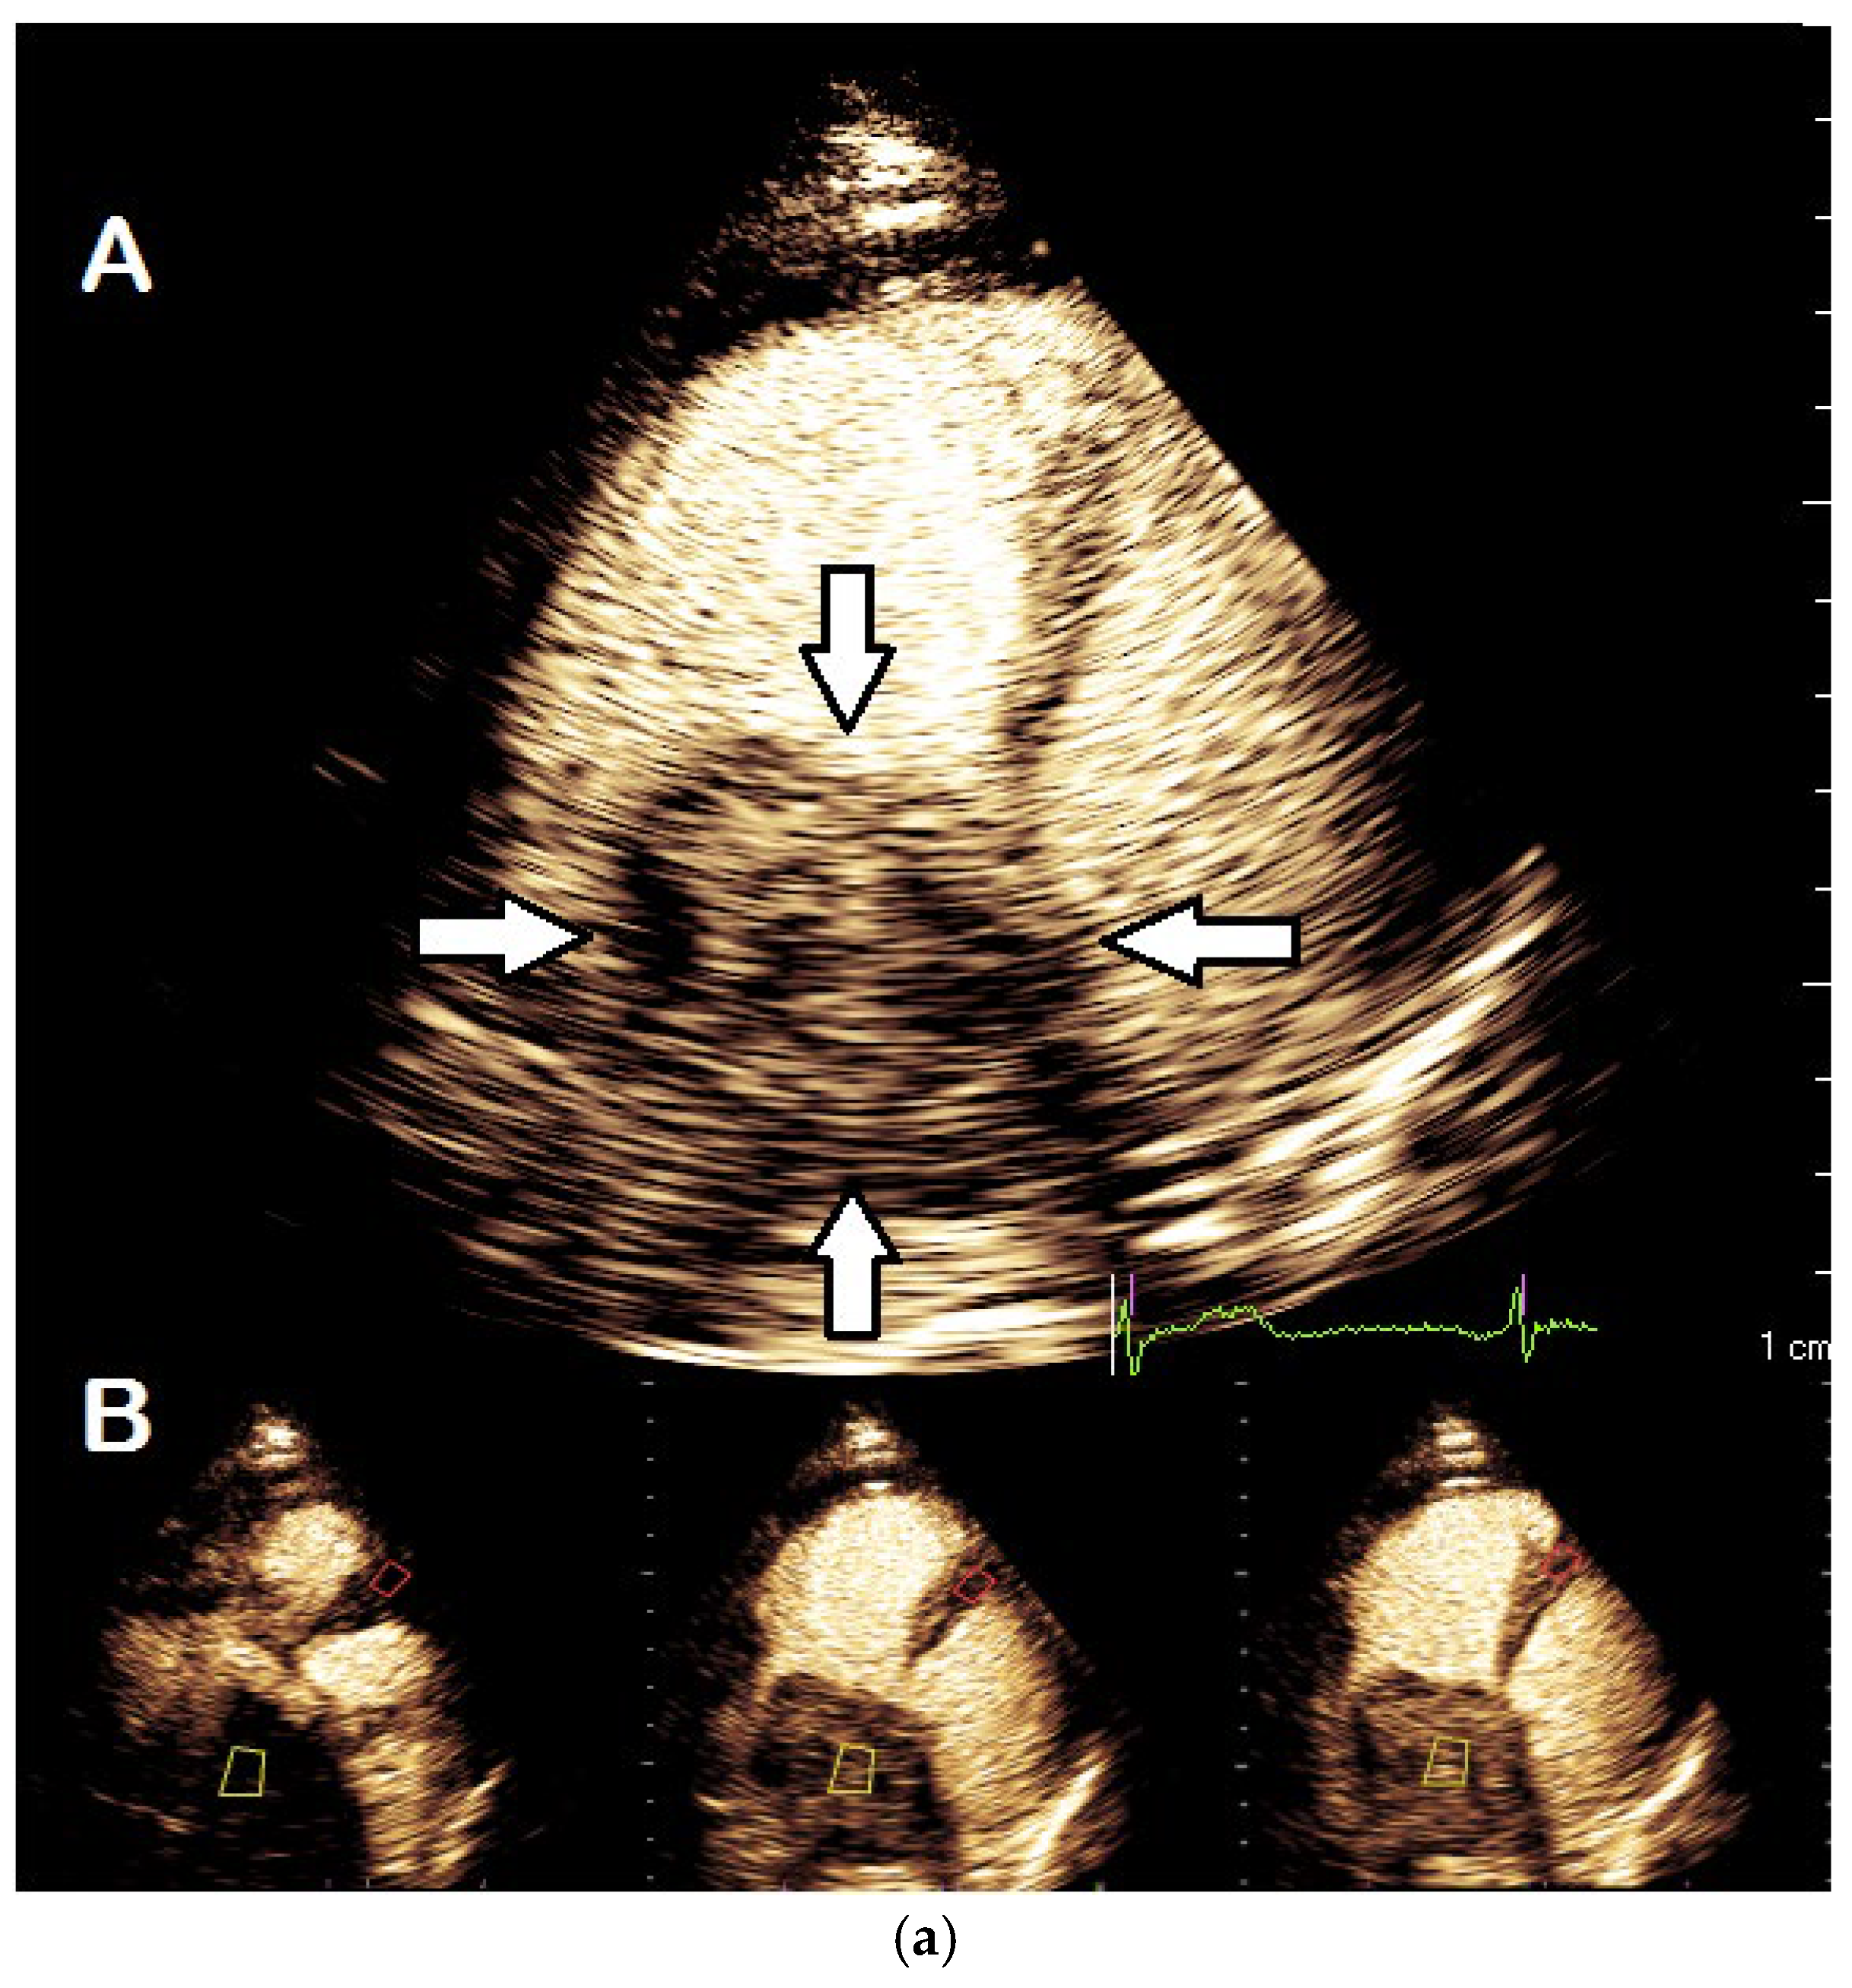

4. Hypertrophic Cardiomyopathy

4.1. Background and Indications

| Imaging method | Low-MI-contrast-specific imaging, additional intermediate-MI imaging in case of apical aneurysm for assessment of thrombus in the aneurysm |

| Imaging planes | Standard apical views and apical sweeps to assess the aneurysm for thrombi |

| Contrast application | Bolus injections |

| Typical finding | 1. Hourglass/ace-of-spades shape of apical LV cavity 2. Apical myocardium appears dark in late systole due to compression of the intramyocardial vessels 3. Apical aneurysms +/− thrombi in some patients |

| Alternative imaging | MRI useful for scar/fibrosis imaging and display of apical aneurysms CT in patients with contraindication for MRI and UEAs |